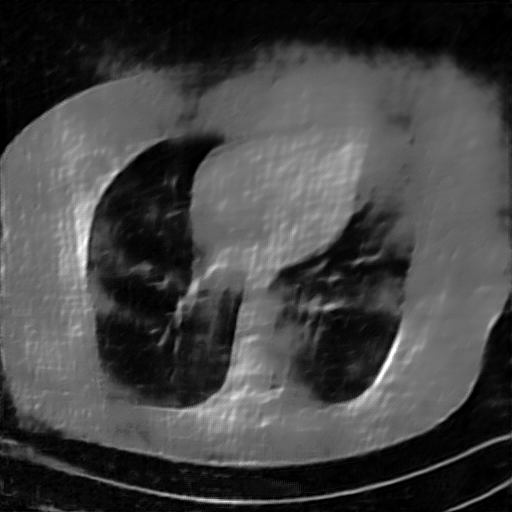

Fig. 4 presents the reconstruction results and residual images obtained by different methods for limited-angle reconstruction. As can be seen, the learning-based methods outperform the direct method and TV model, which exhibit serious artifacts in the missing angle region. Although the denoiser introduced by the FBP-Unet can somehow deal with the noises, the result still presents obvious artifacts. Compared to the SIPID, PD-net and FSR-nets, our LRIP-net1/2 can better preserve the image details and edges with less information left in the residual images. Thus, both the quantitative and qualitative results confirm that the low-to-high double-resolution strategy can improve the reconstruction accuracy for the limited-angle reconstruction problem.

We observe that the low-resolution image prior plays an important role in our method. More specifically, we compare the results of our LRIP-net with respect to different low-resolution priors, which are obtained by down-sampling rate of 1/2, 1/4, and 1/8, respectively. As can be seen in Table III, the best reconstruction results are obtained with the image prior reconstructed by the down-sampling rate of for 150∘, 120∘ and 90∘ limited-angle reconstruction. The visual comparison based on different image priors are also provided in Fig. 5, where obviously less artifacts are left in the reconstruction image by LRIP-net1/8. By comparing the running time, it is easy to see that the smaller the low-resolution image prior, the faster the LRIP-net works.